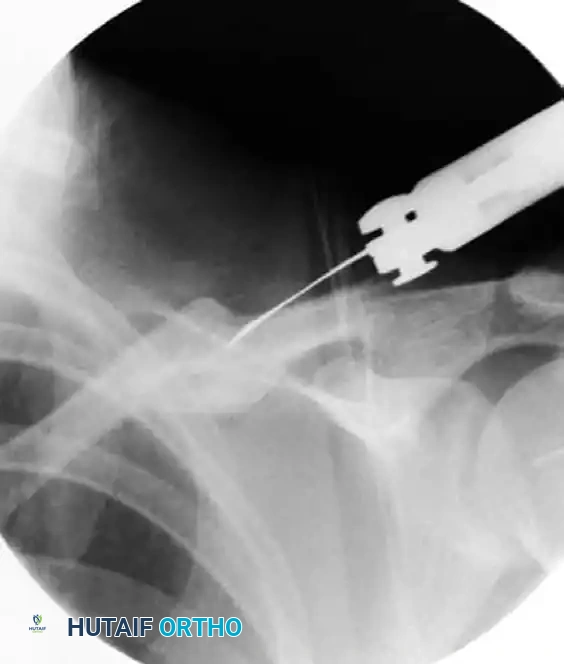

• Nail Advancement: Mount the TEN on a T-handle or a dedicated insertion tool. Advance the nail through the medial fragment until the tip reaches the osteotomy site.

• Reduction and Passage: Manipulate the arm and use reduction forceps (e.g., pointed Weber clamps) at the osteotomy site to anatomically align the medial and lateral fragments. Once reduced, advance the nail across the osteotomy and into the lateral fragment under continuous fluoroscopic control.

Insertion of elastic nail under fluoroscopic control

FIGURE 2: Insertion of the elastic nail under fluoroscopic control. Note the use of reduction forceps to maintain alignment while the nail is advanced across the osteotomy site.

Surgical Warning: Do not force the nail if significant resistance is encountered. Forcing the nail can lead to iatrogenic comminution or perforation of the posterior cortex, placing the subclavian vessels and brachial plexus at catastrophic risk. If resistance is met, withdraw the nail slightly, re-verify the reduction, and ensure the canal is adequately prepared.